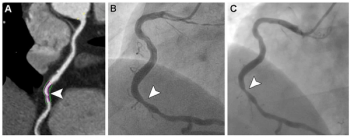

The use of automated detection of large vessel occlusion on computed tomography (CT) through artificial intelligence (AI) software reportedly led to an 11.2-minute reduction in triage time from the completion of imaging to initiation of endovascular therapy, according to newly published research.